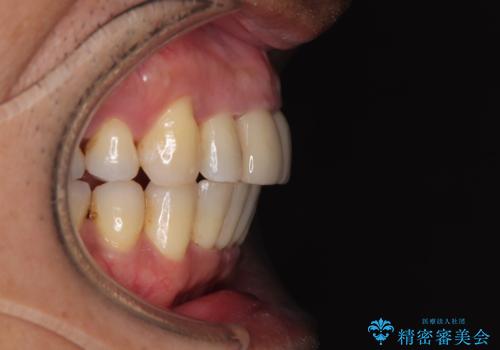

八重歯と突出感を改善 ワイヤー装置での矯正治療

- 八重歯を気にして来院された患者様です。

上顎前歯の突出感と右上の八重歯を気にされていたので、上顎左右の第一小臼歯2本を抜歯し、ワイヤー装置にて矯正治療を行うこととしました。

食いしばりにより奥歯がすり減っており、咬み合わせが定まるまで時間がかかりましたが、整った口もに仕上がりました。